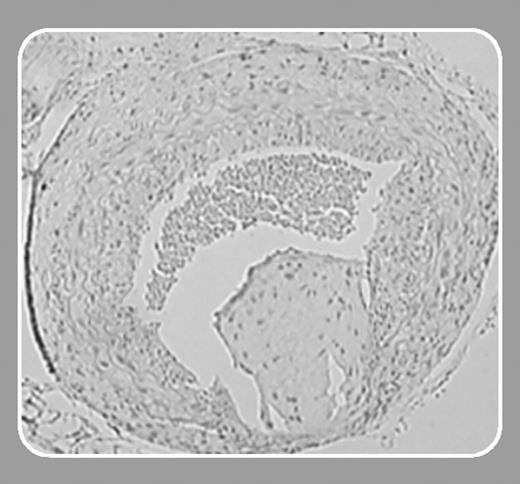

Elevated plasma levels of fibrinogen are strongly associated with human vascular disease. The Northwick Park Heart Study, which prospectively followed more than 1500 men for a mean of 10 years, found that elevated plasma fibrinogen at recruitment was independently associated with subsequent cardiovascular risk, with an increase in baseline plasma fibrinogen of approximately 0.7 g/L (70 mg/dL) being associated with a 39% increase in cardiac death and a 60% increase in nonfatal myocardial infarction.1 However, it is unknown whether elevated plasma fibrinogen plays a causal role in vascular disease progression. On the one hand, elevated plasma fibrinogen may promote vascular disease by increasing blood viscosity, by promoting fibrin formation, by enhancing platelet-platelet interactions, or by other mechanisms. On the other hand, elevated plasma fibrinogen could simply be a marker of vascular disease that in itself does not contribute to disease progression. For example, it is possible that elevated plasma fibrinogen could result from the chronic inflammation that characterizes atherosclerosis. Kerlin and colleagues (page 1728) have examined this important issue by studying thrombosis and vascular disease progression in transgenic mice that carry an extra copy of the murine fibrinogen locus. These Hifib mice have modest (approximately 2-fold) elevations of plasma fibrinogen yet no evidence of underlying inflammation.2 The authors demonstrate that Hifib mice exhibit enhanced fibrin formation under basal conditions, as evidenced by elevated plasma D-dimer levels. In addition, they show that Hifib mice that also carry a loss-of-function mutation in the thrombomodulin gene (TMPro) exhibit enhanced fibrin deposition in the liver compared with wild-type mice or animals with isolated hyperfibrinogenemia or thrombomodulin deficiency. These studies demonstrate that a modest increase in fibrinogen expression can promote fibrin formation in vivo and that the impact of elevated plasma fibrinogen on fibrin deposition within different vascular beds may depend on modifier genes that regulate fibrinogen metabolism.FIG1

Does elevated plasma fibrinogen cause vascular disease? Kerlin et al show that hyperfibrinogenemia alters vascular remodeling induced by ligation of the carotid artery, producing augmented intimal hyperplasia compared with wild-type controls. However, when one considers mechanistic links between hyperfibrinogenemia and coronary heart disease, potential effects on thrombus formation and atherogenesis usually top the list. Interestingly, Kerlin et al found no significant effect of hyperfibrinogenemia on platelet-dependent thrombus formation after carotid artery injury, and previous studies have shown that hyperfibrinogenemia does not accelerate atherogenesis in hyperlipidemic mice.3,4 Therefore, the studies by Kerlin and colleagues are important in that they demonstrate that modest elevations of plasma fibrinogen can alter fibrin formation and modify how blood vessels remodel. A piece of the “cause-and-effect” puzzle has been answered. However, it is still unclear whether modest hyperfibrinogenemia contributes to the development of atherothrombotic diseases—in particular, coronary heart disease and myocardial infarction. Further studies are necessary to resolve this important question.